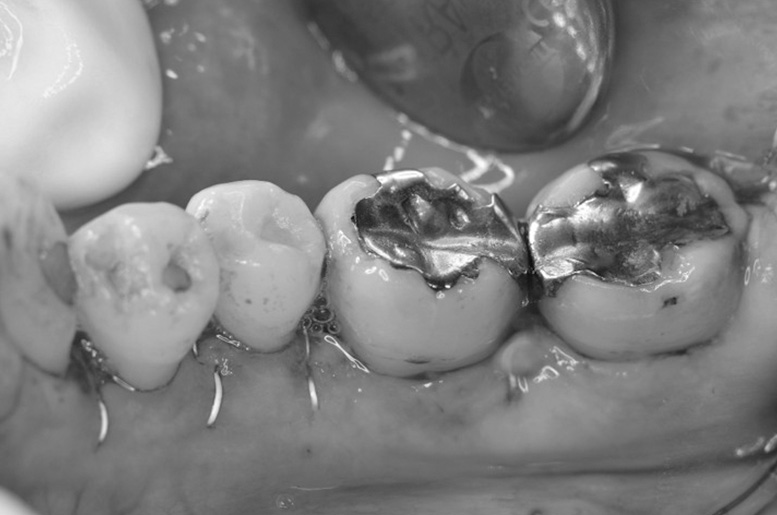

歯周再生療法 精密根管治療 歯周矯正治療 ジルコニアセラミック治療

Before

矯正治療

After

治療期間・回数

約3年・約20回

費用

1,400,000円(歯周矯正治療も含む)

治療のリスク

詰め物・被せ物の調整が難しく、割れた場合は再治療が必要。